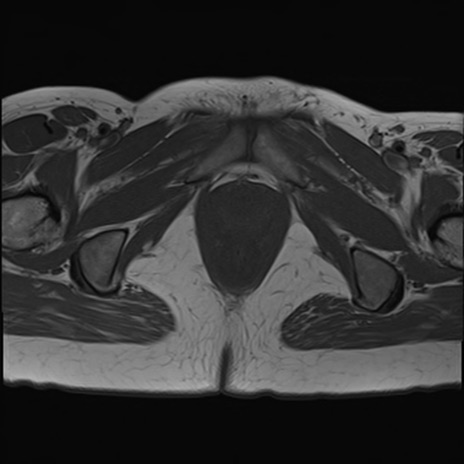

症例39 T1WI(横断像)

MRI(4日後)